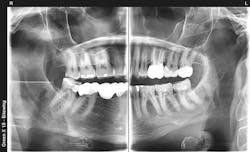

Dental sleep medicine is growing rapidly. Why? A large portion of the adult population in the US has an objectionable snoring problem. Do they want to quit snoring? Of course! Although most physicians place their snoring patients on a CPAP device, many patients are not compliant. Is there another way to stop snoring? Absolutely. You can do so with a well-made snoring appliance (figures 1 and 2).

Do you just start doing this procedure? No. Like any other new procedure, continuing education is a must. The American Academy of Dental Sleep Medicine can help you get started with information and course suggestions.

When you eliminate sleep issues from patients, they are extremely grateful. You feel a sense of satisfaction, and you’ve incorporated some needed diversity in your practice. Dental sleep medicine is an important part of dental practice, and when you’re competent with the procedures, you’ll be pleased you did so.